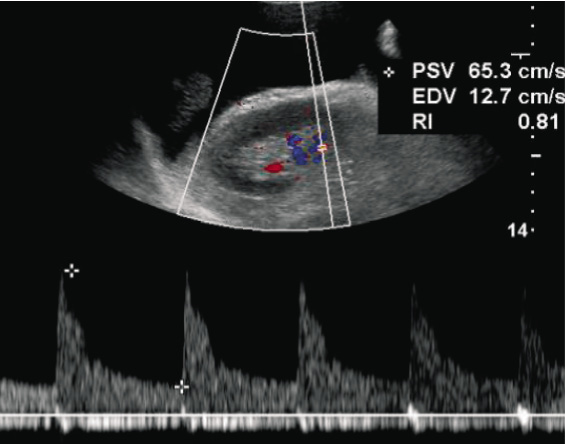

Figura 3. Ecodoppler renale con indici di resistenza intraparenchimali aumentati.

L’ecodoppler dei vasi renali evidenzia indici di resistenza intra-parenchimali marcatamente aumentati (RRI 0,81-0,84) (Figura 3); all’ecografia dei vasi epiaortici emergono diffusi ispessimenti con placche non emodinamicamente significative (<30%) alla biforcazione carotidea bilateralmente.